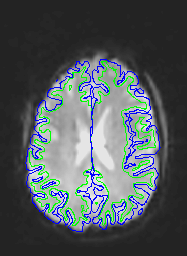

Here are uncorrected EPI images with the same boundaries overlaid.

Note that this is not a problem of subject motion: inhomogeneities in the magnetic field in the head (create by the tissue properties) creates the distortion. The best way to remove distortion is to measure the magnetic field in the scanner (creating a B0 map) and use it to unwarp the EPI images. Because this is not commonly done, a second choice is to distort the EPI images so that they match the T1 image. This is done in AFNI using the 3dAllineate program.